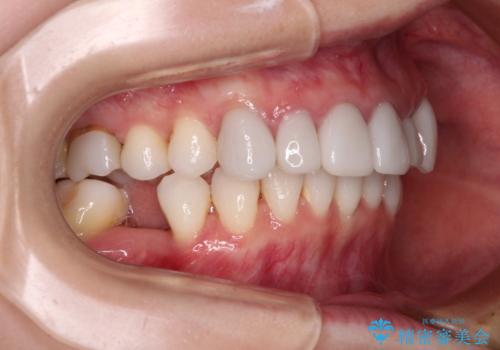

- 全体的なデコボコと、奥歯の欠損を放置した結果倒れ込んだ奥歯などを気にして来院された患者様です。

ワイヤー矯正の方が理想的な仕上がりとできる状態でしたが、上顎前歯にクラウンが装着されているため、インビザラインにて矯正治療を行うこととしました。

インビザラインのみで対応できないときにはワイヤー矯正を併用することとし、矯正治療後にはオールセラミッククラウンによる補綴治療を行うこととしました。

矯正治療自体はインビザラインで満足のいく仕上がりとなりました。

前歯は根管治療が必要となり、元々舌側に入り込んでいた左上2番目の歯は歯周外科処置により歯肉ラインを整えることとしました。

欠損部位は傾斜歯軸を起き上がらせることができたため、オールセラミッククブリッジにて補綴治療を行いました。

全顎的に満足のいく仕上がりとなりました。